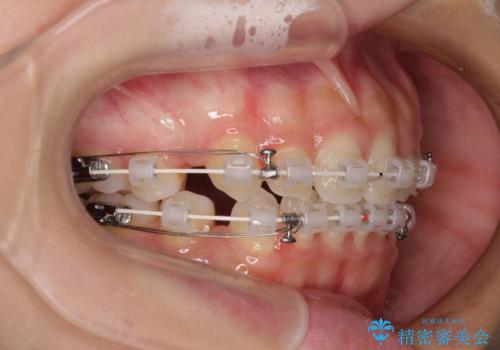

前歯のデコボコとクロスバイト ワイヤー装置での抜歯矯正

- 前歯のデコボコとクロスバイトを気にして来院された患者様です。

上下ともにデコボコはそれほど強くありませんでしたが、非抜歯では口元が突出した仕上がりとなる可能性があるため、上下左右の第一小臼歯4本を抜歯し、ワイヤー装置での抜歯矯正を行うこととしました

スペースを閉じるために期間を要しましたが、無事に綺麗な口元に仕上げることができました。